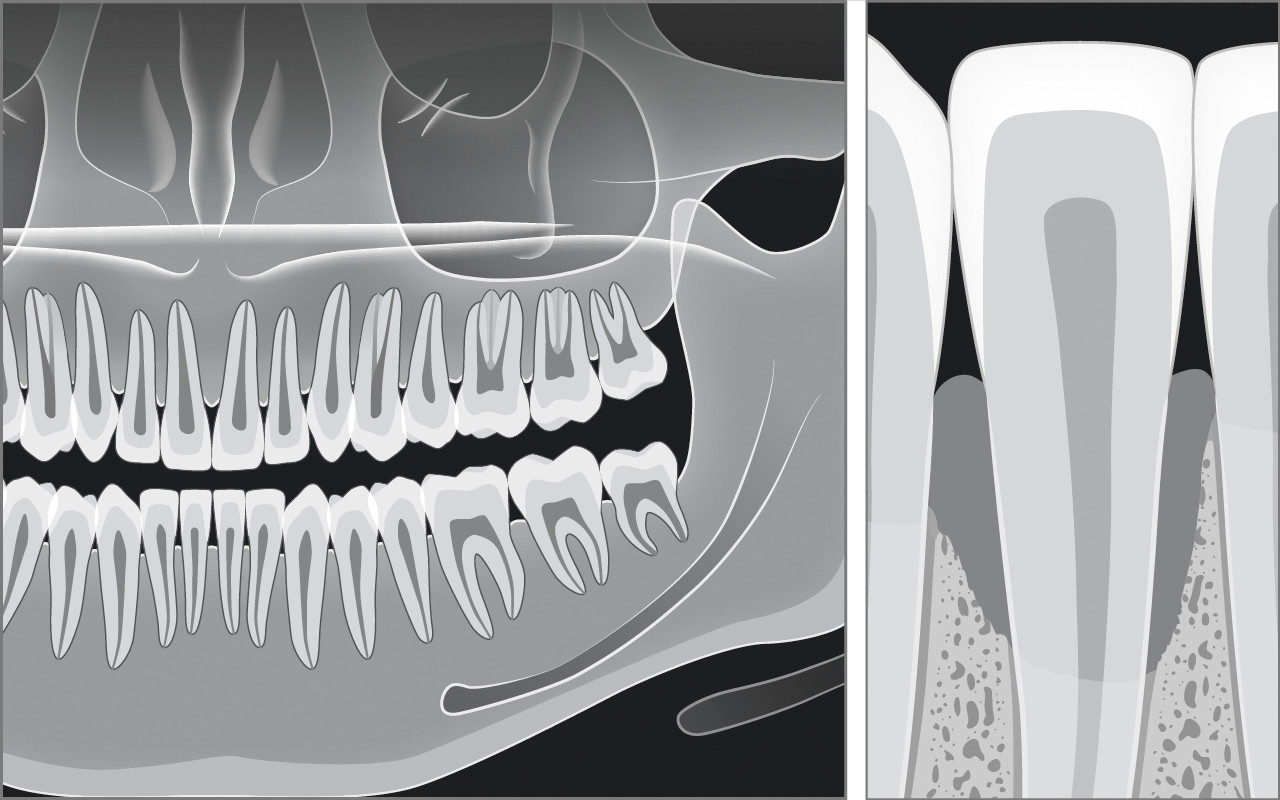

Röntgenbefund

Die Messungen mit der Parodontalsonde können Stellen im Gebiss mit grösseren Sondierungstiefen aufspüren, die eine zusätzliche Beurteilung durch eine Röntgenaufnahme erfordern.

Die Diagnose Parodontitis kann erst mit den notwendigen Röntgenaufnahmen definitiv bestätigt werden. Die Wahl der zur parodontalen Diagnostik notwendigen Röntgenbilder kann erst nach der klinischen Untersuchung erfolgen. Dadurch kann eine unnötige Strahlenbelastung vermieden werden.

Ein Röntgenbefund besteht im einfachsten Fall aus 2 Aufnahmen (Bissflügelaufnahmen) und im umfangreichsten Fall aus einem so genannten Röntgenstatus mit bis zu weiteren 14 Röntgenbildern oder einem Panorama-Röntgenbild. Die angefertigten Röntgenbilder müssen den den Zahn umgebenden Kieferknochen zeigen und eine Einschätzung des Schweregrades des Knochenabbaus erlauben.

Bei jeder in der Zahnarztpraxis angefertigten Röntgenaufnahme muss das Gebiss sowohl auf Karies als auch auf Parodontitis kontrolliert werden.